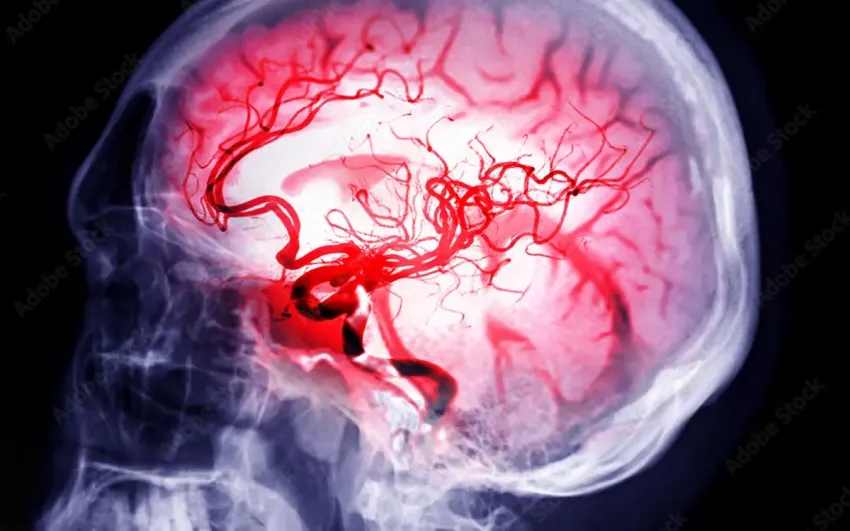

Los casos de derrame cerebral están aumentando, especialmente en personas jóvenes… y esta es la razón

Los neurólogos de todo el mundo alertan sobre un aumento de derrames cerebrales en jóvenes. Aunque el ictus se ha asociado históricamente a la vejez, los datos más recientes demuestran que la tendencia está cambiando de forma acelerada y preocupante.

Un análisis global publicado en The Lancet Neurology mostró que, de 1990 a 2021, la incidencia de ictus en personas menores de 55 años creció, mientras que en mayores se estancó. En jóvenes, el aumento fue más notable en países de ingresos medios y bajos.

Un informe de los CDC reveló que los adultos entre 45 y 64 años experimentaron un incremento del 15 % en la prevalencia de accidente cerebrovascular entre 2011 y 2022; en el grupo 18‑44 años el alza fue del 14,6 %.

Según la revisión publicada en Journal of Clinical Medicine, los ictus en menores de 50 años ya representan el 10‑14 % de todos los accidentes cerebrovasculares en Estados Unidos y Europa, con una tendencia ascendente constante.